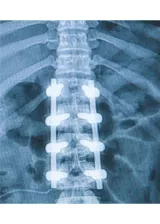

Spinal fusion is a procedure where two or more vertebrae are “welded” together to strengthen the spine and prevent motion in areas of pain. Abigail Eldridge-Nickerson knows the surgery well. After four years of trying everything from physical therapy to cortisone injections to deal with her sciatica, she had parts of her spine fused together to eliminate the discomfort.

Tufts MC surgeons have embraced a unique approach to pain control during spinal fusion– an added step where a dose of a non-narcotic analgesic called liposomal bupivacaine is injected into the muscles around the incision area, just as the surgery is being completed.